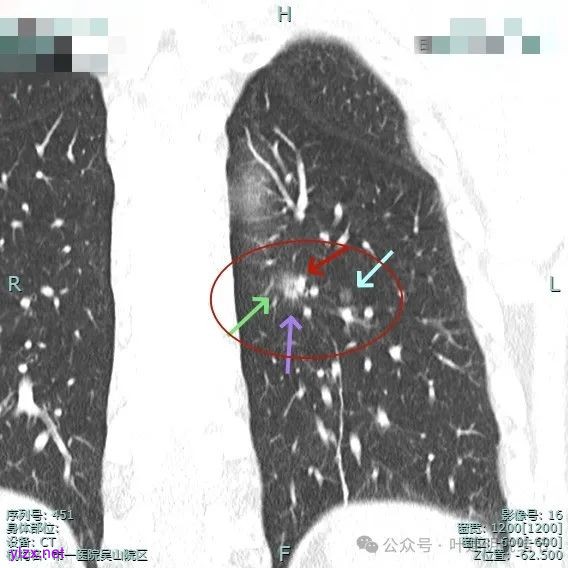

手术组再三考虑,由于即使主病灶仍磨玻璃成分为主,是符合指南亚肺叶切除的指征的,如果能想办法定位后楔形切除,不按肺段解剖切,不单手术方便,而且也容易保留更多肺组织。所以与患方商量并沟通后,我们仍选择定位后的楔形切除,术前请影像科沈起钧主任定位,用医用胶定:

上图蓝色箭头所指的是医用定位胶,天蓝色箭头是次病灶,红色箭头是主病灶,设计的切除线如虚线所示。我们打算进胸后确定定位胶所在平面,因为包括两处病灶均在同一平面上,然后我们游离下肺韧带,将后基底段此部分肺组织向下解剖游离开,直到下肺静脉下缘,并贴着下叶静脉边缘往肺实质深面用切割缝合器切开并闭合肺切缘,按CT上大概距离推算,到越过次病灶深度后转向胸肋面,切除该范围内的肺组织。